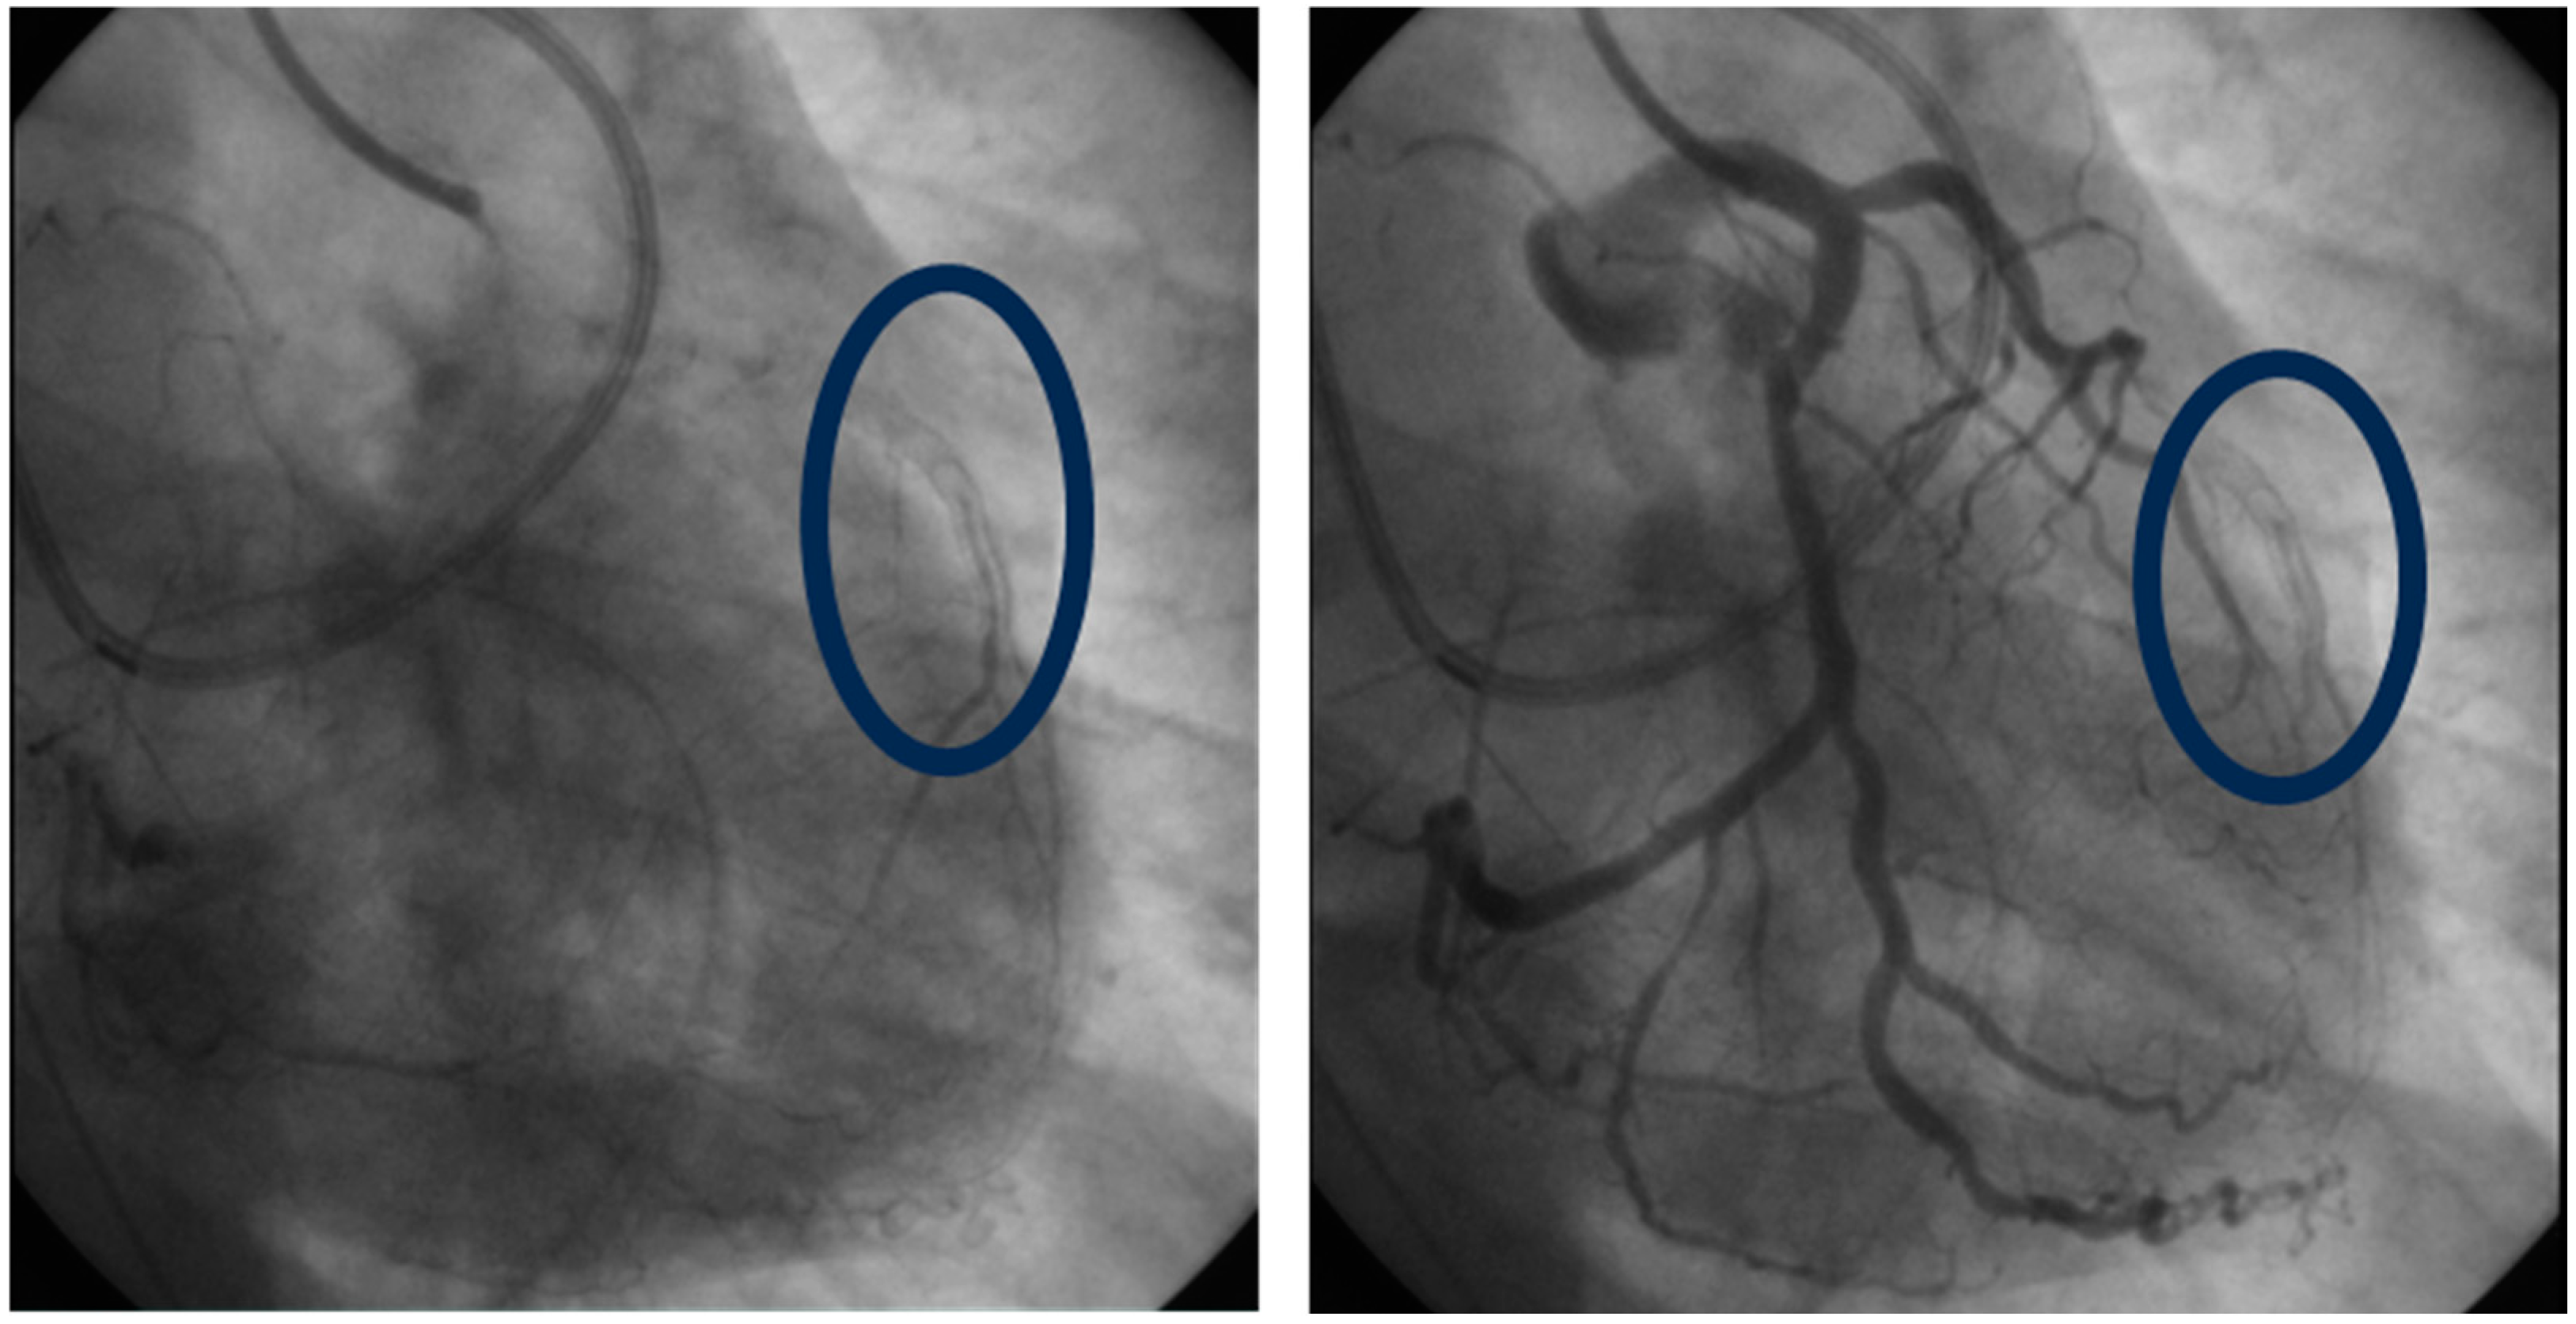

2.2. Lp(a) and In-Stent Restenosis

3.4. Lp(a) and In-Stent Restenosis

- Wehinger, A.; Kastrati, A.; Elezi, S.; Baum, H.; Braun, S.; Neumann, F.-J.; Schömig, A. Lipoprotein(a) and coronary thrombosis and restenosis after stent placement. J. Am. Coll. Cardiol. 1999, 33, 1005–1012. [Google Scholar] [CrossRef]

- Ribichini, F.; Steffenino, G.; Dellavalle, A.; Vado, A.; Ferrero, V.; Camilla, T.; Giubergia, S.; Uslenghi, E. Plasma Lipoprotein(a) Is Not a Predictor for Restenosis After Elective High-Pressure Coronary Stenting. Circulation 1998, 98, 1172–1177. [Google Scholar] [CrossRef]

- Khosravi, A.; Pourmoghaddas, M.; Ziaie, F.; Enteshari, A.; Khaledifa, A.; Bahonar, A. Does Lipoprotein (a) Level Have a Predictive Value in Restenosis after Coronary Stenting? Int. J. Prev. Med. 2011, 2, 158–163. [Google Scholar]

- Qin, S.-Y.; Liu, J.; Jiang, H.-X.; Hu, B.-L.; Zhou, Y.; Olkkonen, V.M. Association between baseline lipoprotein (a) levels and restenosis after coronary stenting: Meta-analysis of 9 cohort studies. Atherosclerosis 2013, 227, 360–366. [Google Scholar] [CrossRef]

- Kamitani, T.; Taniguchi, T.; Miyai, N.; Kawasaki, T.; Kawasaki, S.; Sugihara, H. Association Between Plasma Lipoprotein(a) Concentration and Restenosis After Stent Implantation. Circ. J. 2005, 69, 644–649. [Google Scholar] [CrossRef]

- Yuan, X.; Han, Y.; Hu, X.; Jiang, M.; Feng, H.; Fang, Y.; Liu, M.; Chen, Y.; Gao, L. Lipoprotein (a) is related to In-Stent neo-atherosclerosis incidence rate and plaque vulnerability: Optical Coherence Tomography Study. Int. J. Cardiovasc. Imaging 2022, 39, 275–284. [Google Scholar] [CrossRef] [PubMed]

- Mahmoud, A.K.; Farina, J.M.; Awad, K.; Ali, N.B.; Pereyra, M.; Scalia, I.G.; Abbas, M.T.; Allam, M.N.; A Kamel, M.; A Abu Rmilah, A.; et al. Lipoprotein(a) and long-term in-stent restenosis after percutaneous coronary intervention. Eur. J. Prev. Cardiol. 2024. [CrossRef]